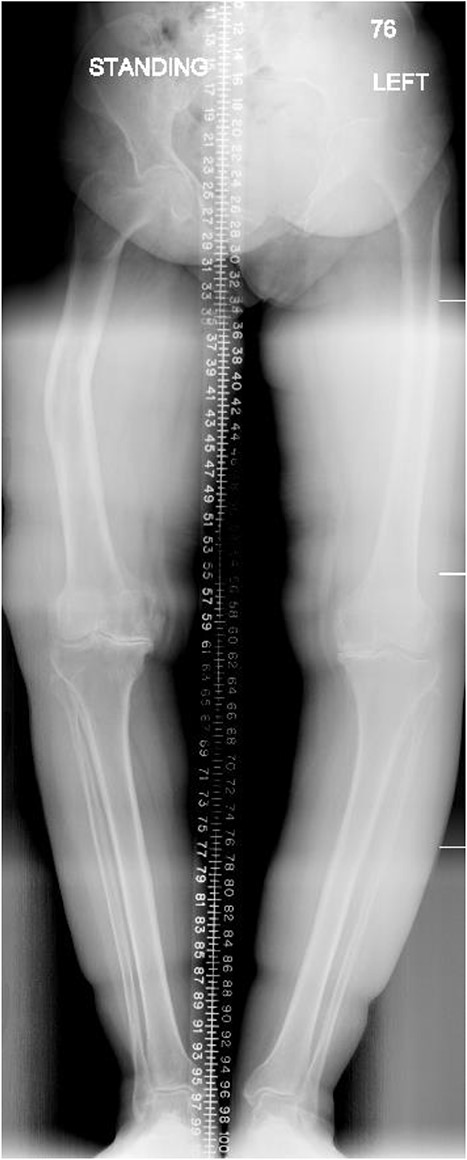

A 66-year-old woman with a history of right femoral shaft fracture, which was managed conservatively and resulted in malunion with right varus knee deformity. At the age of 54 years, she was diagnosed with osteoarthritis, and conservative treatment options, including weight reduction, non-steroidal anti-inflammatory medications, physiotherapy and intra-articular steroid injections, had been exhausted. Knee pain continued to worsen over the years, with negligible improvement in her symptoms. On physical examination, there was obvious varus deformity of the right knee, and significant restriction in the range of motion from full extension to 90° flexion. X-rays were requested, which revealed severe tri-compartmental knee osteoarthritis, a 3 cm medial shift of the right lower-limb mechanical axis, and 80° anatomical lateral distal femoral angle (aLDFA) and 96° mechanical lateral distal femoral angle (mLDFA) (Figs 1 and 2). The findings were discussed with the patient, who agreed to proceed with TKA. Given the complexity of this case with the femur deformity, the CORI Smith & Nephew surgical arthroplasty system was recommended as the surgical option that was suited to the patient’s specific bony anatomy and appropriate positioning of the components.

Preoperative anteroposterior standing bilateral lower extremity radiographs displaying long leg alignment and the right femur Varus deformity.